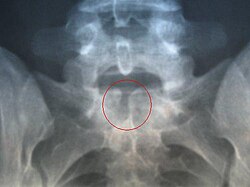

De acuerdo con un artículo publicado por Mayo Clinic, la espina bífida es una afección que ocurre cuando la columna vertebral y la médula espinal no se forman adecuadamente:

Puede variar de ser leve a causar discapacidades graves:

“Los síntomas dependen del lugar en la columna vertebral en donde se encuentra la abertura y su tamaño”.